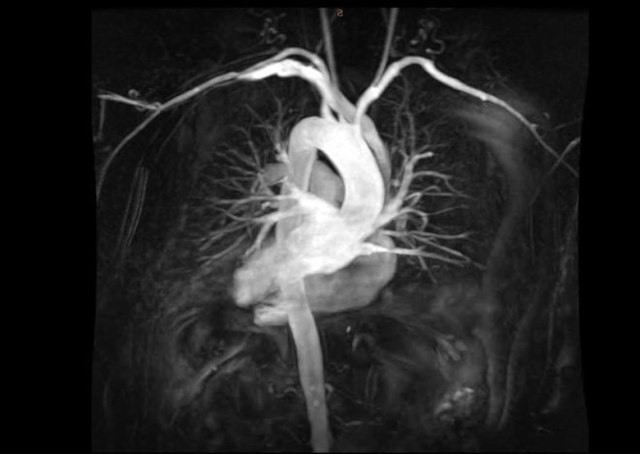

В сентябре 2019 г наш МРТ томограф был укомплектован еще одной современной радиочастотной катушкой, что позволило СДЦ не только значительно улучшить визуализацию изображений при МРТ исследованиях, но и проводить уникальные для Самары и России медицинские исследования МРТ ангиографию лёгочных артерий, артерий верхних и нижних конечностей.

Самарский диагностический центр предлагает альтернативу в этой безвыходной ситуации для специалиста и пациента — МРТ ангиографию сосудов. При этом полностью исключается воздействие вредного ионизирующего излучения и побочных реакций от введения рентгеноконтрастного препарата на организм человека.

Благодаря инновационной технологии, внедренной в СДЦ–кардиологи и сосудистые хирурги получат результаты исследований своих пациентов (ангиография лёгочных артерий, артерий верхних и нижних конечностей) даже при непереносимости пациентами контрастных препаратов на основе йода.